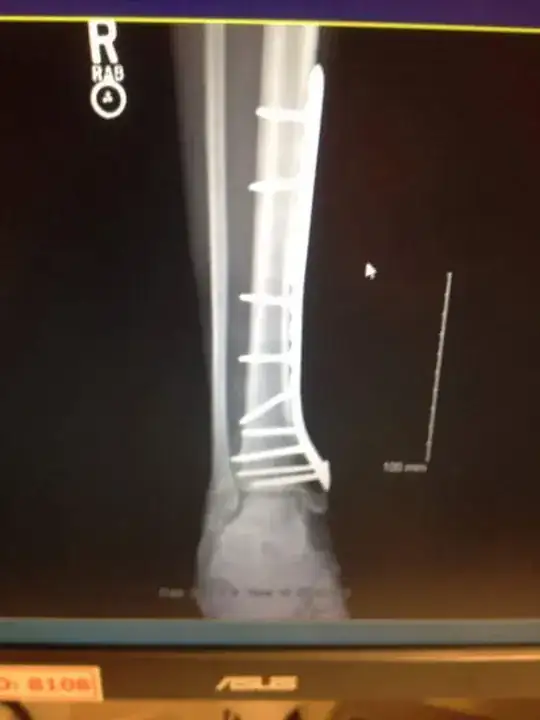

I had a pilon fracture; it's the plate that causes pain. Get it removed. enter image description here